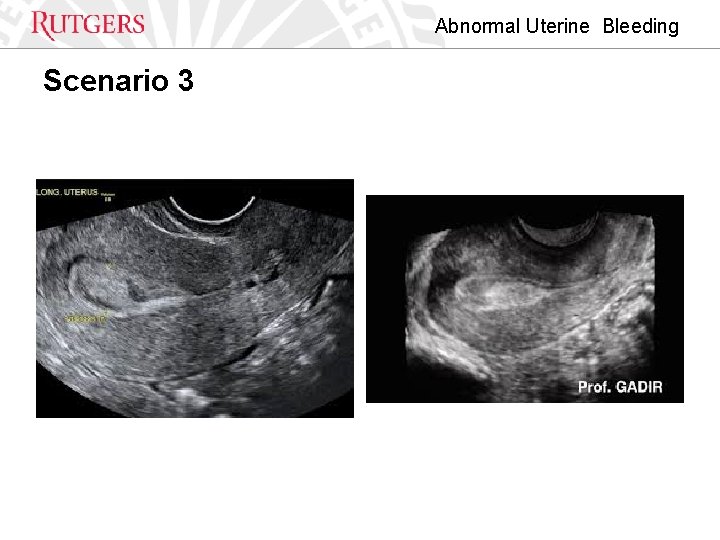

Abnormal Uterine Bleeding Scenario 3

Abnormal Uterine Bleeding Polyp • Lesions usually benign • Atypical or malignant features rare • Present or absent

Abnormal Uterine Bleeding Polyp • Identification – – – Dimensions Location Number Morphology Histology

Abnormal Uterine Bleeding Leiomyoma • • Benign fibromuscular tumors of the myometrium Prevalence up to 70% Caucasian and 80 - % women with African Ancestry Primary Classification – Present or Absent Secondary – Involving Endometrial Cavity • Tertiary – Sub endometrial – Submucososal – Size Baird DD, Dunson DB, Hill MC, et al. High cumulative incidence of uterine leiomyoma in black and white women: ultrasoundevidence. Am J Obstet Gynecol 2003; 188: 100 e 7.

Abnormal Uterine Bleeding Adenomyosis • • • Relationship between adenomyosis and AUB is unclear Prevalence is 5%-70% Endometrial tissue beneath the endometrial –myometrial interface Identified by histopathology by hysterectomy specimen MRI Ultrasound